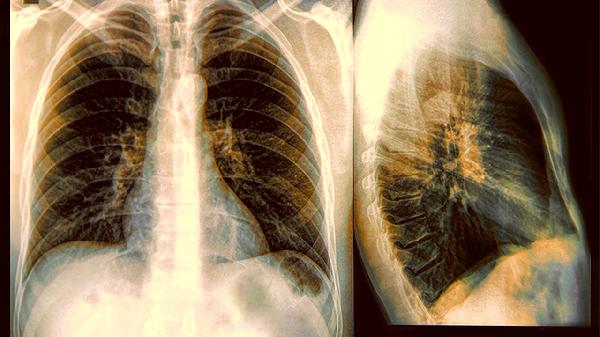

一、肺癌类型决定起跑线差距

1.小细胞肺癌vs非小细胞肺癌

小细胞肺癌就像失控的跑车,确诊时七成已经转移,生存期往往以月计算。非小细胞肺癌里的肺腺癌就像慢性子老头,部分早期患者手术后能活过十年。

二、确诊时机是生死分水岭

1.早期发现的幸运儿

肺结节阶段就逮住癌细胞,做个微创手术可能就根.治了。可惜多数人咳嗽咯血才就诊,这时候癌细胞早就像蒲公英种子飘满全身。